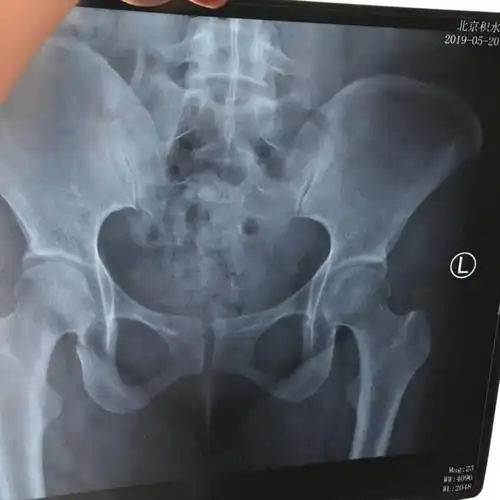

产后耻骨联合分离,松动,响